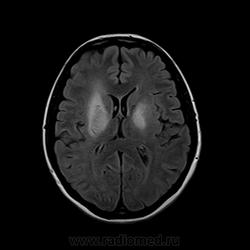

Здравствуйте уважаемые коллеги! Помогите пожалуйста разобраться. Пациентка 38лет, с 1999г. СКВ, гормозависимость, инвалид 3гр. На данный момент клинически атаксия, дизартирия, дисфагия, ригидность мышц туловища. На основании Мр картины моя коллега из частной МР-клиники сделал заключение: болезнь Вильсона-Конвалова. У меня возникли сомнения, т.к. нет подтверждающих лабораторных данных (церрулоплазмин в пределах нормы). Мы повторно выполнили МРТ головного мозга с контрастным усилением, картина анлогичная. В общем похоже на Вильсона-Коновалова (гепатолентикулярная дегенерация), но при БКВ в первую очередь поражаются хвостатое ядро и скорлупа, а в данном случае преимущественно внутрення капсула, а скорлупа практически не затронута.

Не складывается впечатление про Вильсона.

Поражение затрагивает, в большей степени, полуовальные центры и другое белое вещество. Так же затронут один бледный шар.

Такая картина часто наблюдается при осмотической демиелинизации. При СКВ бывает нарушение секреции антидиуретического гормона, можно эту тему попытаться развить.

конечно отложение железа в скорлупе справа имеет место, но в данном случае на первое место выходит выраженное симметричное поражение полуовальных центров и внутренних капсул. я согласен с коллегами по поводу демиелинизации при СКВ.